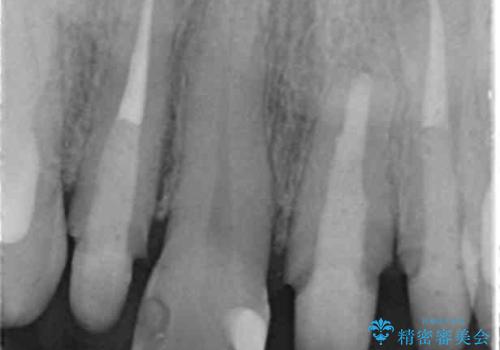

- 前歯のクラウンの歯肉の位置が年々変化し、歯ぐきのフチが黒くなってしまった、綺麗にしたいと希望されて来院されました。

装着されているセラミッククラウンを除去したのち、現在の歯ぐきのラインにしっかりと合う精度の高いオールセラミッククラウンを作製していきます。

- 39.6万円(ジルコニアクラウン×3・仮歯×3)費用は治療当時の料金となります